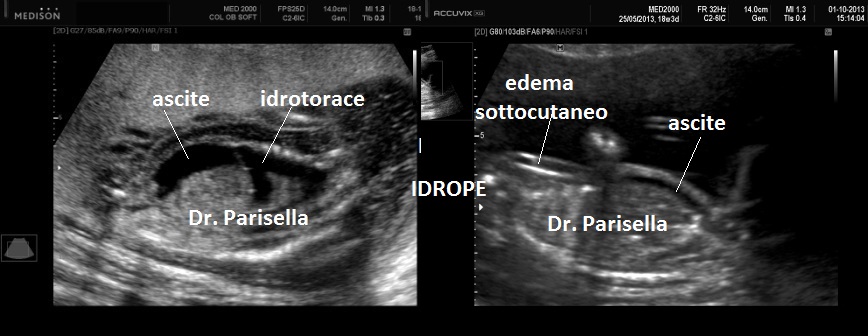

I segni principali sono la micromelia marcata, l'idrope fetale e ossificazioni ectopiche.

2. idrope fetale